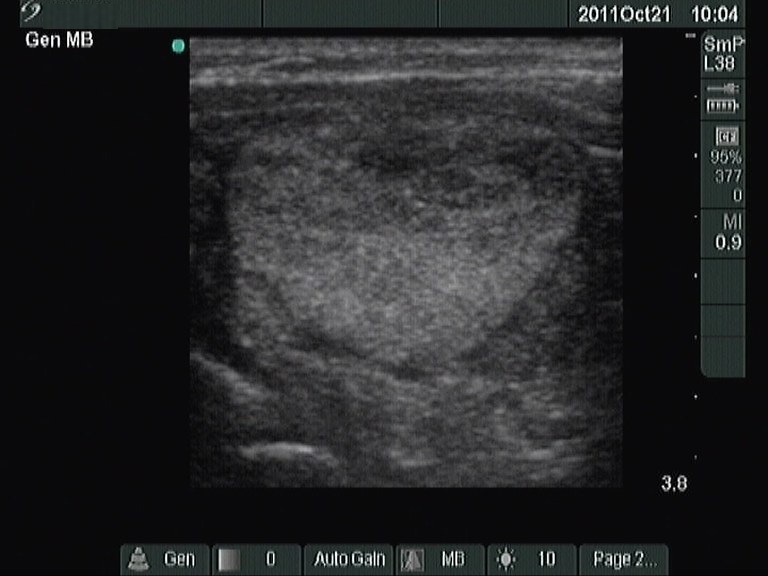

Right lobe, longitudinal scan

Left lobe, longitudinal scan. The nodule exhibits a halo sign.